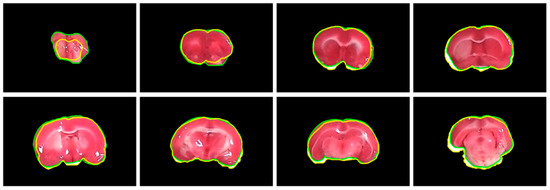

4.4. Evaluation of Rat Hemisphere Segmentation